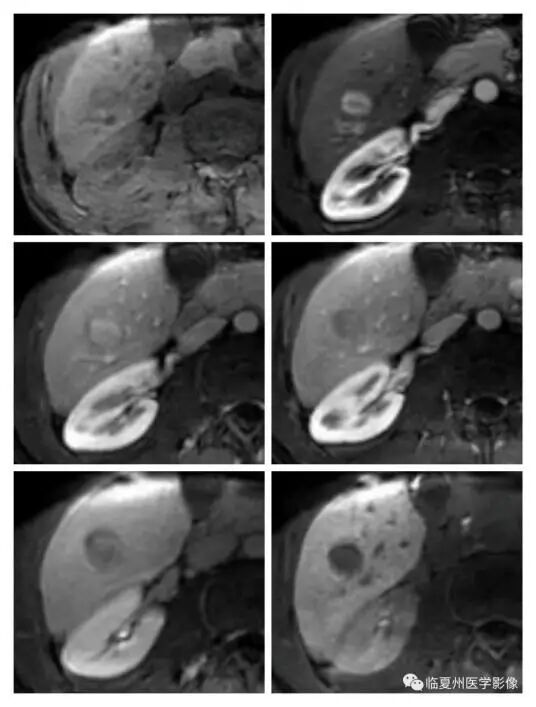

42岁的张先生在做CT检查时,发现肝右叶后下段有一个低密度结节,医生为其做了CT平扫及CT增强检查,只见肝右叶后下段有一枚直径约18毫米的稍低密度灶,定性诊断不明确,无法排除肝癌的可能性。为进一步明确病灶性质,我院磁共振室团队为其实行肝胆特异性造影剂——钆塞酸二钠MRI增强检查,检查后明确诊断为“小肝癌”。目前患者正积极准备行早期根治术。

肝特异性造影剂检查后,肝脏结节定性诊断更加精准,使肝癌病灶无所遁形。

钆塞酸二钠(Gd-EOB-DTPA)是一种肝胆特异性MRI对比剂,除具有普通磁共振造影剂动态增强特点外,其独特的肝胆特异期显象功能可以提高对肝脏局灶性病变的检出及定性诊断能力,尤其对微小病灶(直径<1.0cm)的检出和鉴别诊断具有优势。使用肝细胞特异性对比剂钆塞酸二钠(Gd-EOB-DTPA)可提高直径≤1.0cm肝癌的检出率以及对肝癌诊断与鉴别诊断的准确性,可明显提高小肝癌的诊断敏感性,同时有助于鉴别高度异型增生结节等癌前病变。